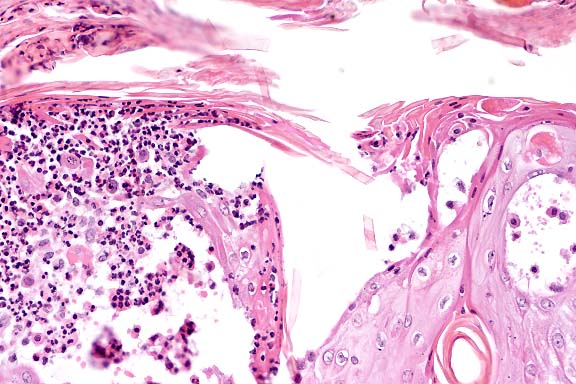

Case 29-2. Skin. Junction between normal skin and squamous cell carcinoma that has not broken through the basement membrane (in situ). Some sloughing superficial necrotic debris is on the surface. 4X

Contributor's Diagnosis and Comments: Squamous cell carcinoma in situ (Bowen's disease).

Squamous cell carcinoma (SCC) in situ is considered to be a premalignant condition. In humans, SCC in situ has been associated with an internal malignancy or arsenic exposure. This form of squamous cell carcinoma does not require ultraviolet light exposure and a sparsely haired/poorly pigmented skin for its development, as is seen in most cases of SCC in the cat which has a predilection for eyelids, ears and planum nasale. We do not know if there is any relationship between the presence of the mediastinal thymoma and hepatoma and the development of these lesions.

SCC in situ has been associated with papillomavirus infection in the cat. The virus has been demonstrated by immunohistochemical methods in the lesions. No evidence of virus was detected on histopathology, but immunohistochemistry was not undertaken.

AFIP Diagnosis: Haired skin: Squamous cell carcinoma in situ, Domestic Shorthair, feline.

Conference Note: Immunohistochemical procedures to detect human papilloma viruses were applied to this tissue at the AFIP, but results were negative.

SCC in situ is considered to be rare in cats and very rare in dogs.2 Clinically, affected animals present with one or more erythematous, pigmented, nodular plaques which may be eroded or ulcerated. The plaques are well demarcated from the surrounding haired skin. Lesions may occasionally show local invasion or microinvasion, but metastasis has not been reported. Older cats are most often affected, and there is no known breed predilection.

SCC in situ is distinguished from actinic keratosis primarily on clinical grounds, i.e. actinic keratosis affects only sun-exposed, lightly pigmented skin. A histologic feature of actinic keratosis which is not seen in this case is fragmentation and replication of elastin fibers.